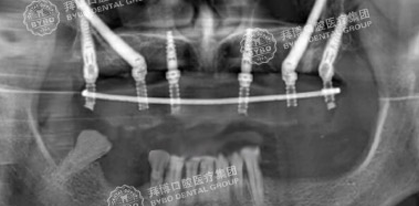

通过计算机断层CT口腔体检,获取口腔的三维数据,3D精准化定位详细测量牙床的骨质密度、牙槽骨本身的高度、宽度等条件;模拟显示种植体在牙槽骨的位置,生成可视化的数据模板。根据数据模板由计算机辅助设计的种植手术导板,从而大大的监控种植牙手术的安全性和准确性。

牙齿种植案例展示 TAIKANG BYBO DENTAL